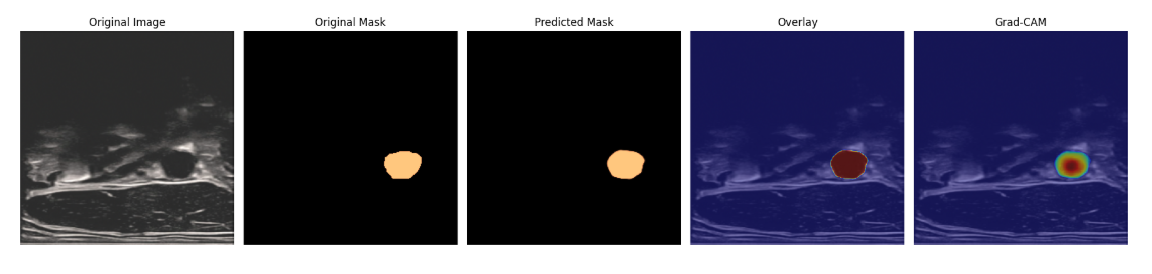

预测的部分结果展示: